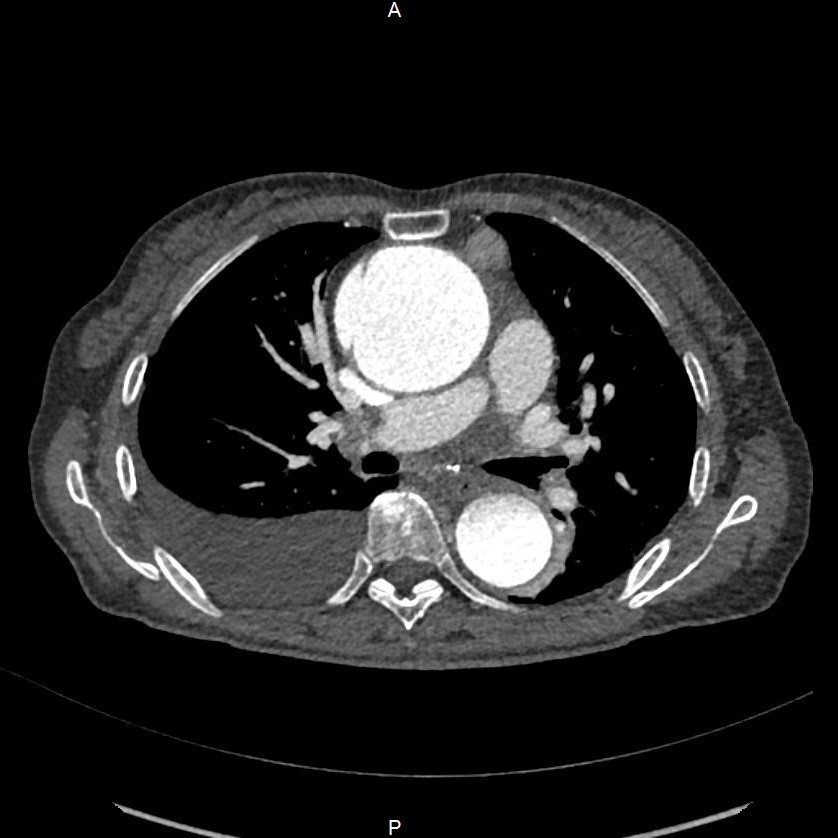

11月下旬,一位60多岁的女性患者因严重胸闷、气急被送入新华医院奉贤院区急诊。检查发现,患者升主动脉瘤样扩张至6.5cm,远超正常范围,且合并主动脉夹层,如同一颗“不定时炸弹”,随时面临破裂风险。同时,患者还伴有重度主动脉瓣关闭不全、大量胸腔积液及心力衰竭,病情复杂且危急。

图4:升主动脉显著扩张合并夹层,还提示胸腔积液